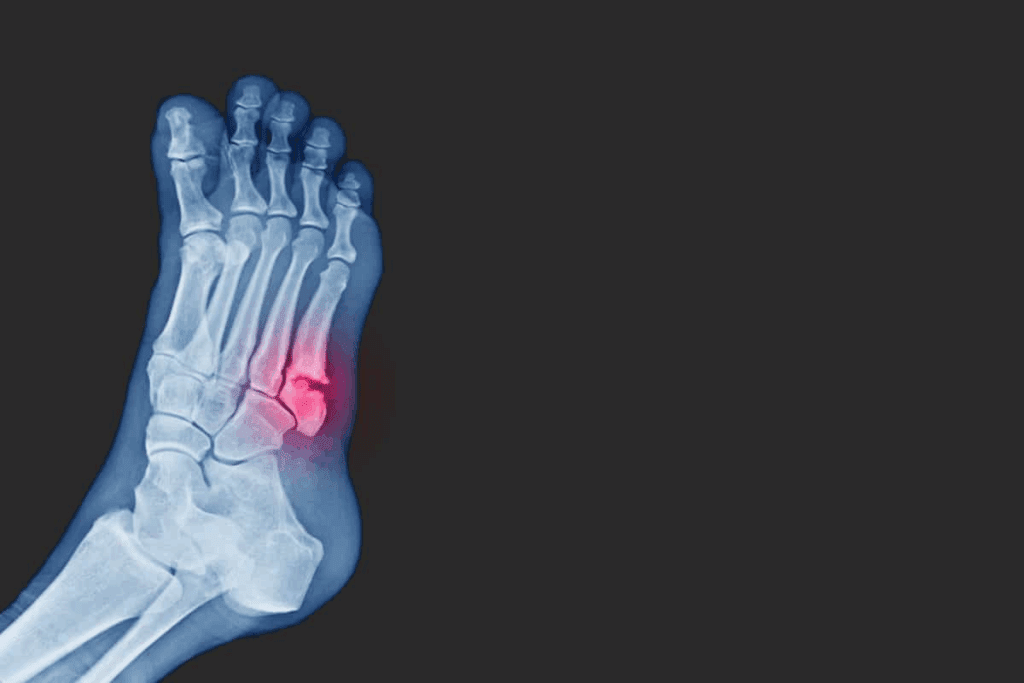

Lower Extremity Fracture Complications

Fractures in the legs, ankles, and feet have their own challenges. Complications can include:

- Difficulty bearing weight on the affected limb

- Increased risk of deep vein thrombosis (DVT)

- Chronic pain or instability in the ankle or knee

Lower extremity fractures are serious because these limbs bear our weight. Issues like osteomyelitis, an infection of the bone, can be very dangerous if not treated quickly.